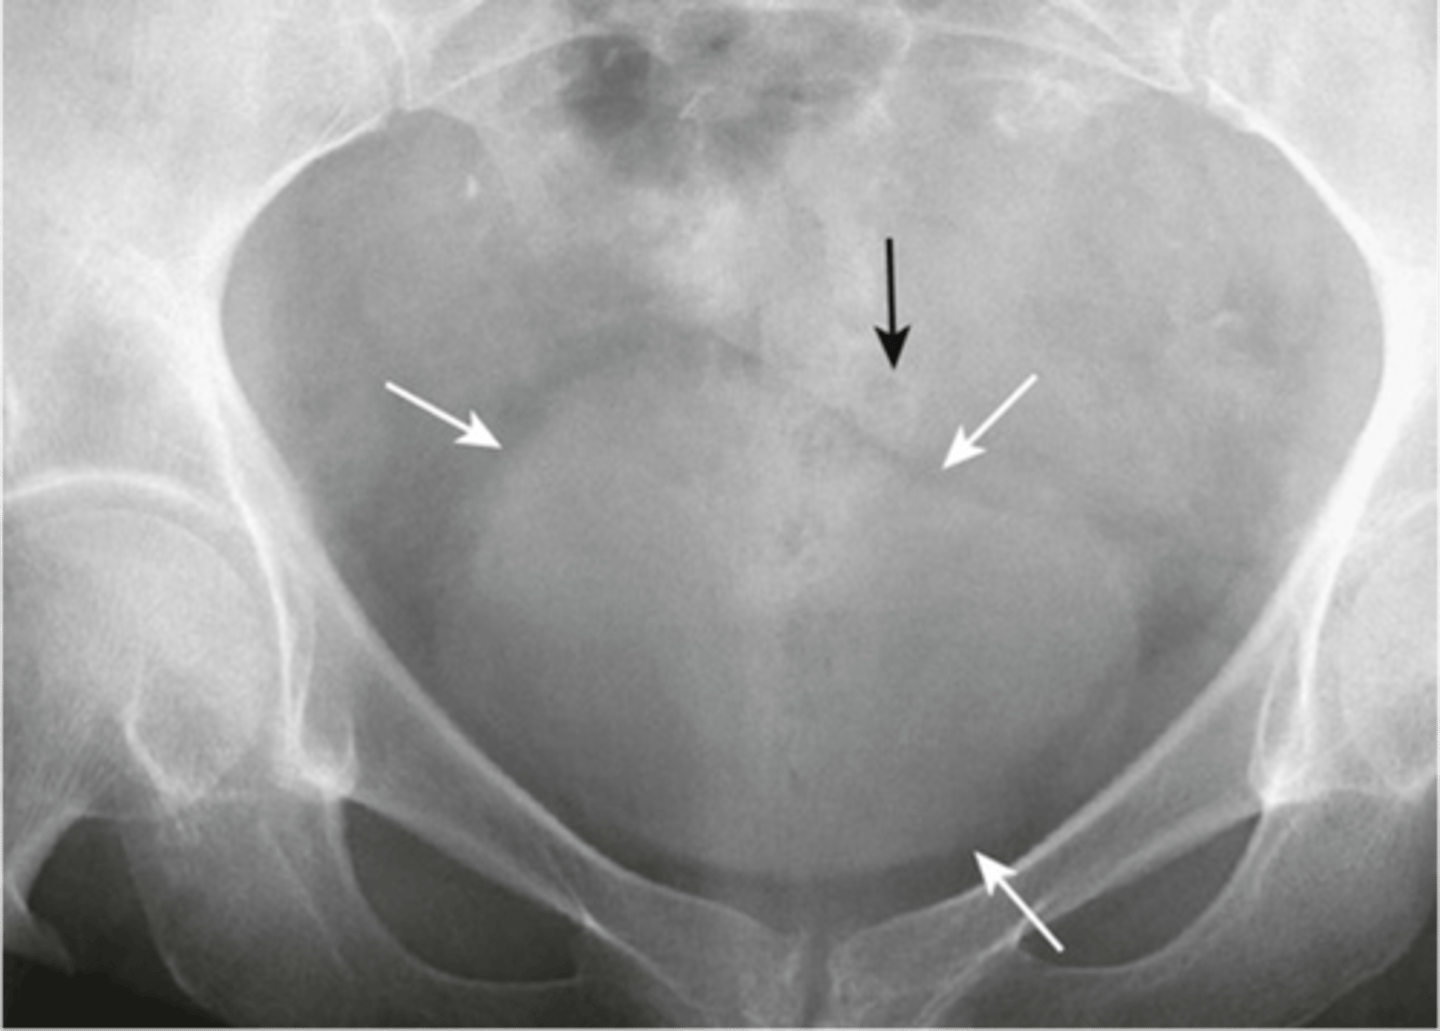

Normal bladder

left: distended bladder

right: enlarged uterus